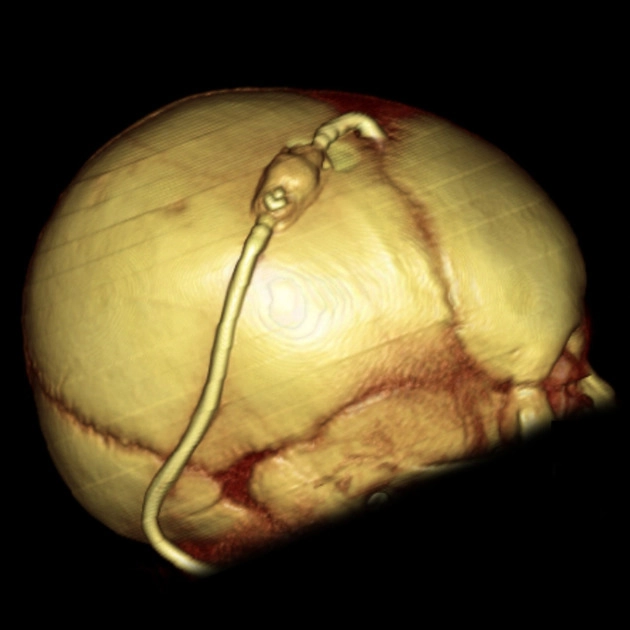

• Dẫn lưu não thất-phúc mạc (Ventriculoperitoneal Shunt - VP)